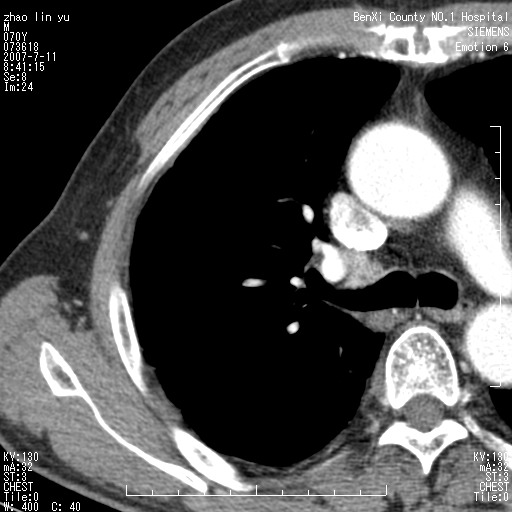

以下是引用王靖旗在2007-7-10 17:12:00的发言:[br] 男、70、咳嗽两个月,半年前换瓣手术,胸片未见异常,于昨天行x片发现右肺上野大片影,行ct扫描,这里是减薄图像,余肺正常。明天晚上会有增强扫描片,到时我会上传。[br][br] 冠状位请大家细看,应该是有意义的,[br][br] 请大家先看平扫发表意见。[br][br]

[br]冠状面[br]

以下是引用zhangzhongshou在2007-7-10 21:43:00的发言:[br]右肺上叶周围型肺癌,以孤立型细支气管肺泡癌可能性大。